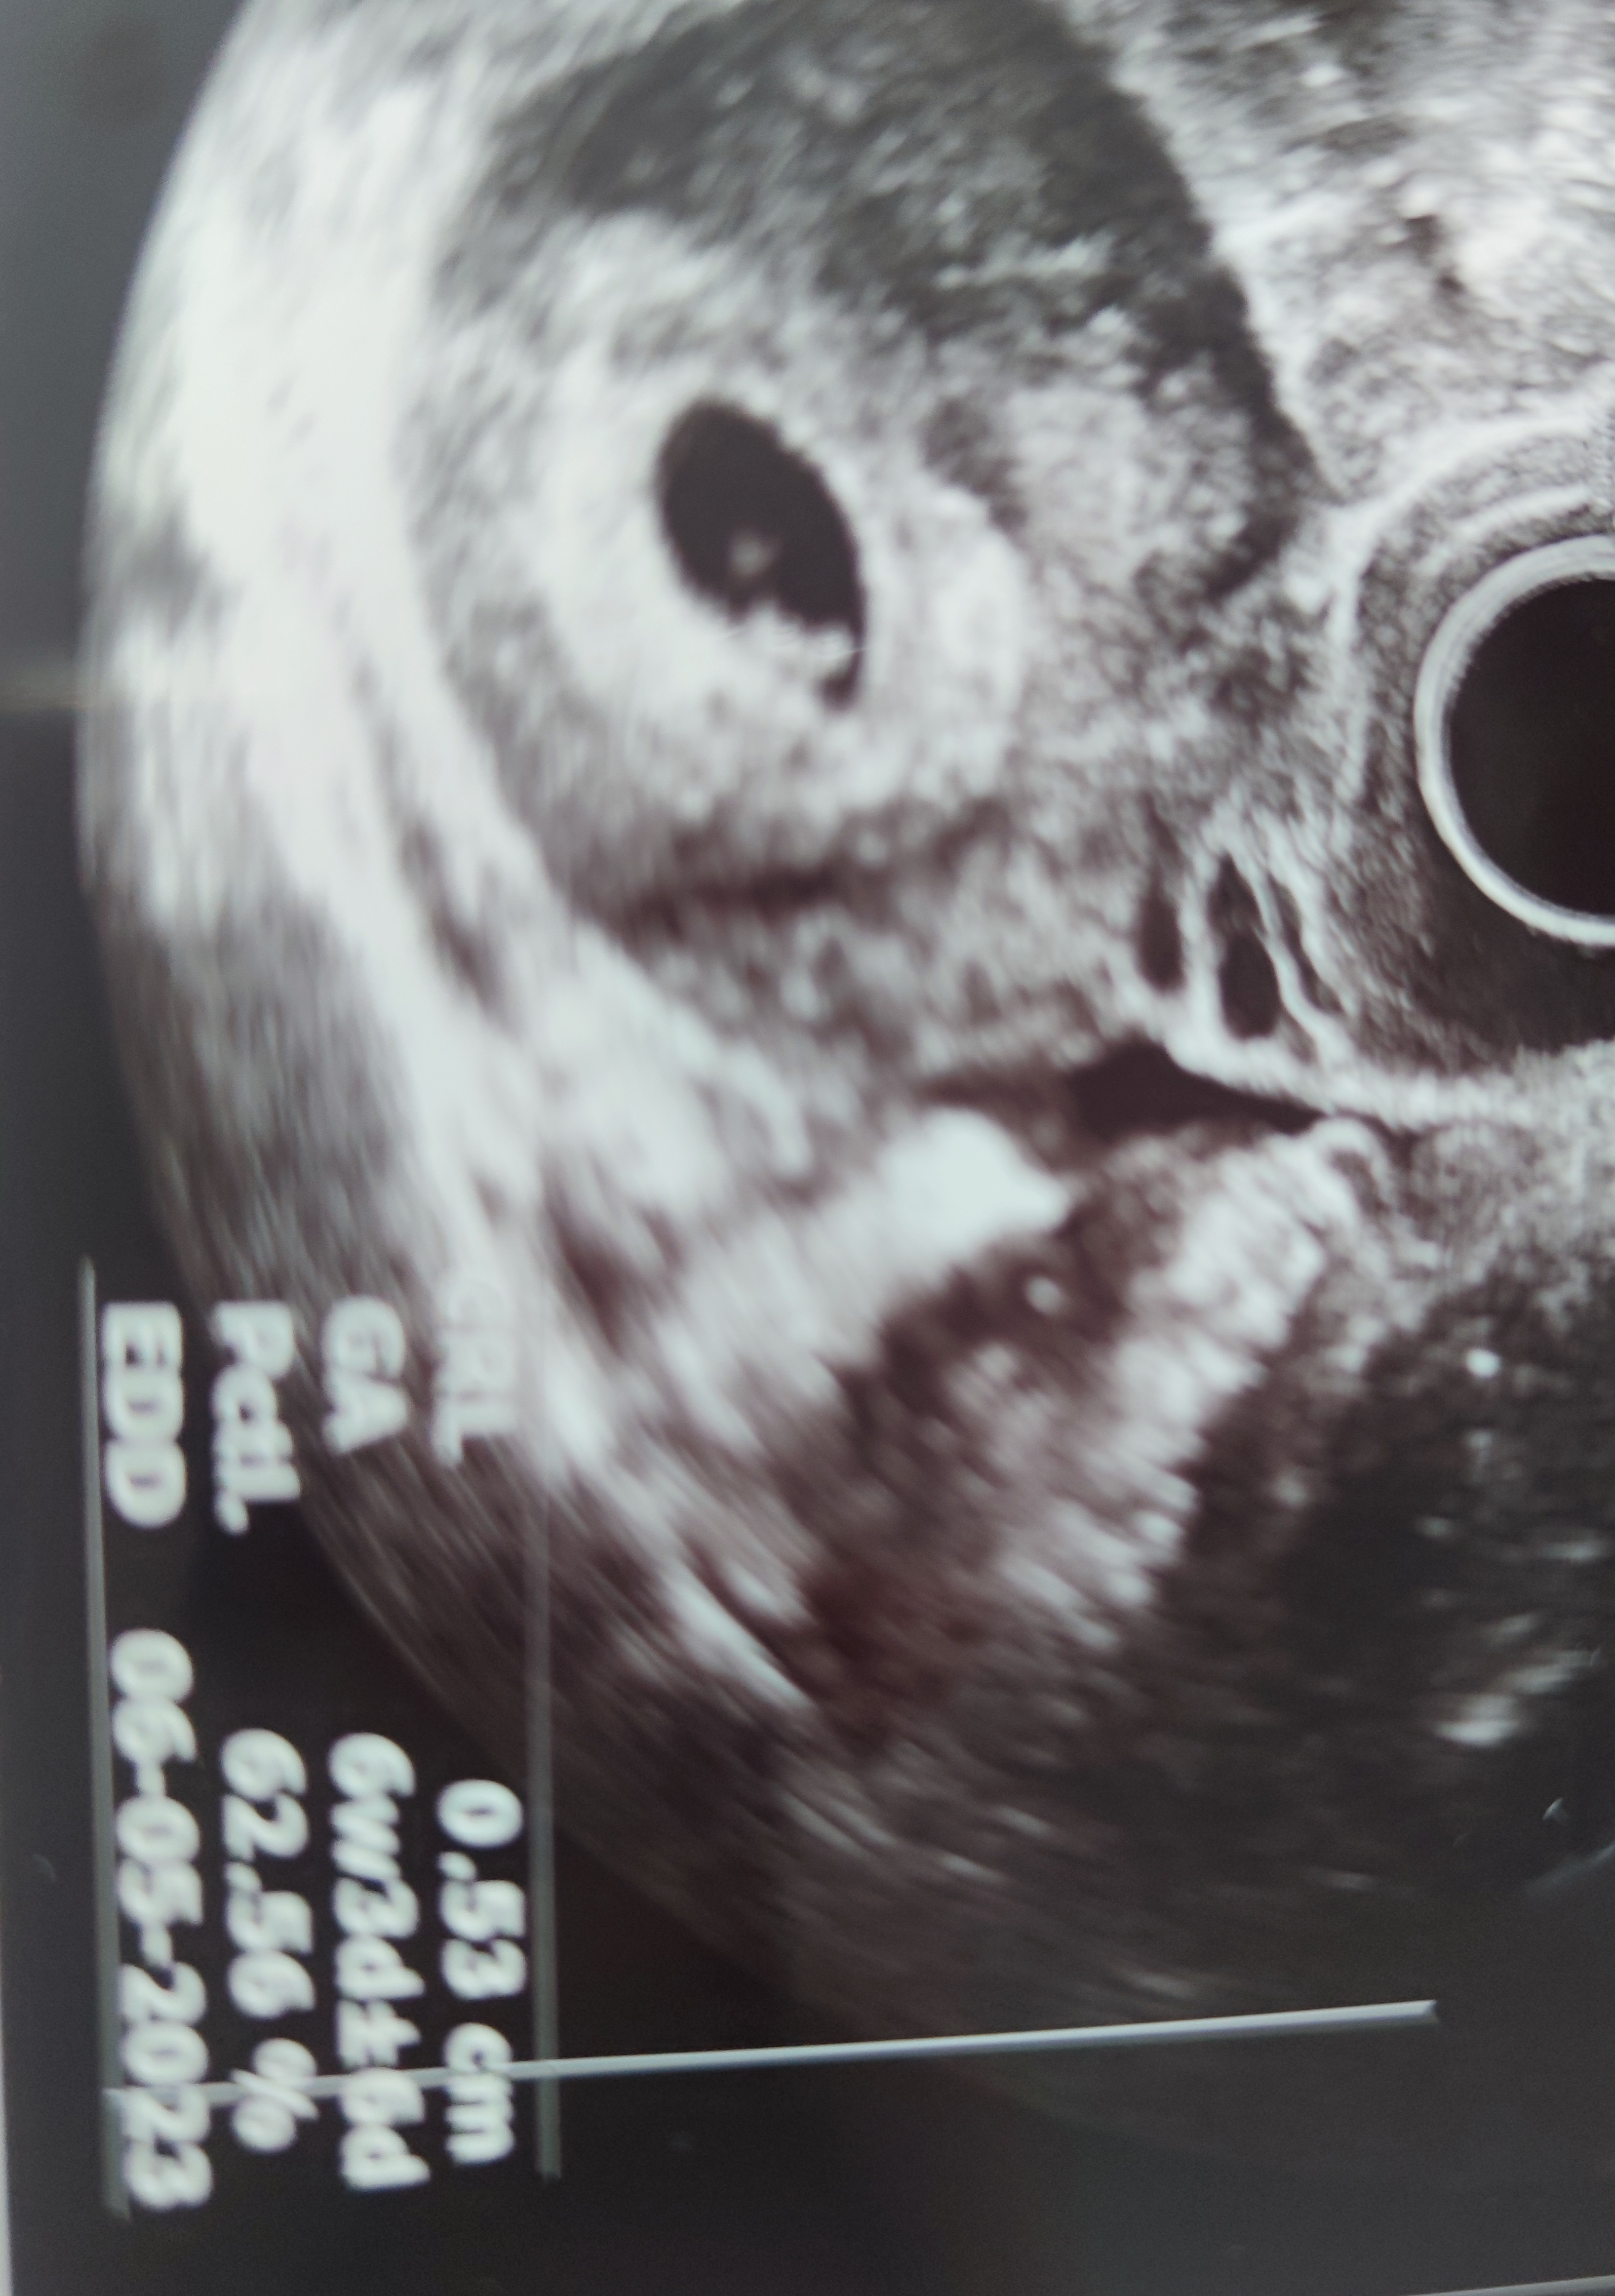

Gratuluje serduszka i dobrze, że ta krew to tylko fałszywy alarm!U mnie też serduszko i 1.39 cmwg USG 7 tydzień 5 dzień czyli wychodzi termin na kwiecień

Ufff../ całe szczęście. GratulujeU mnie też serduszko i 1.39 cmwg USG 7 tydzień 5 dzień czyli wychodzi termin na kwiecień

Myślę że mogę do was dołączyćwczoraj na USG zarodek 0.5mm

serducho uwidocznione. Termin na 6.05.

Coś wspaniałego:* rosnijcie zdrowo !Witajcie.